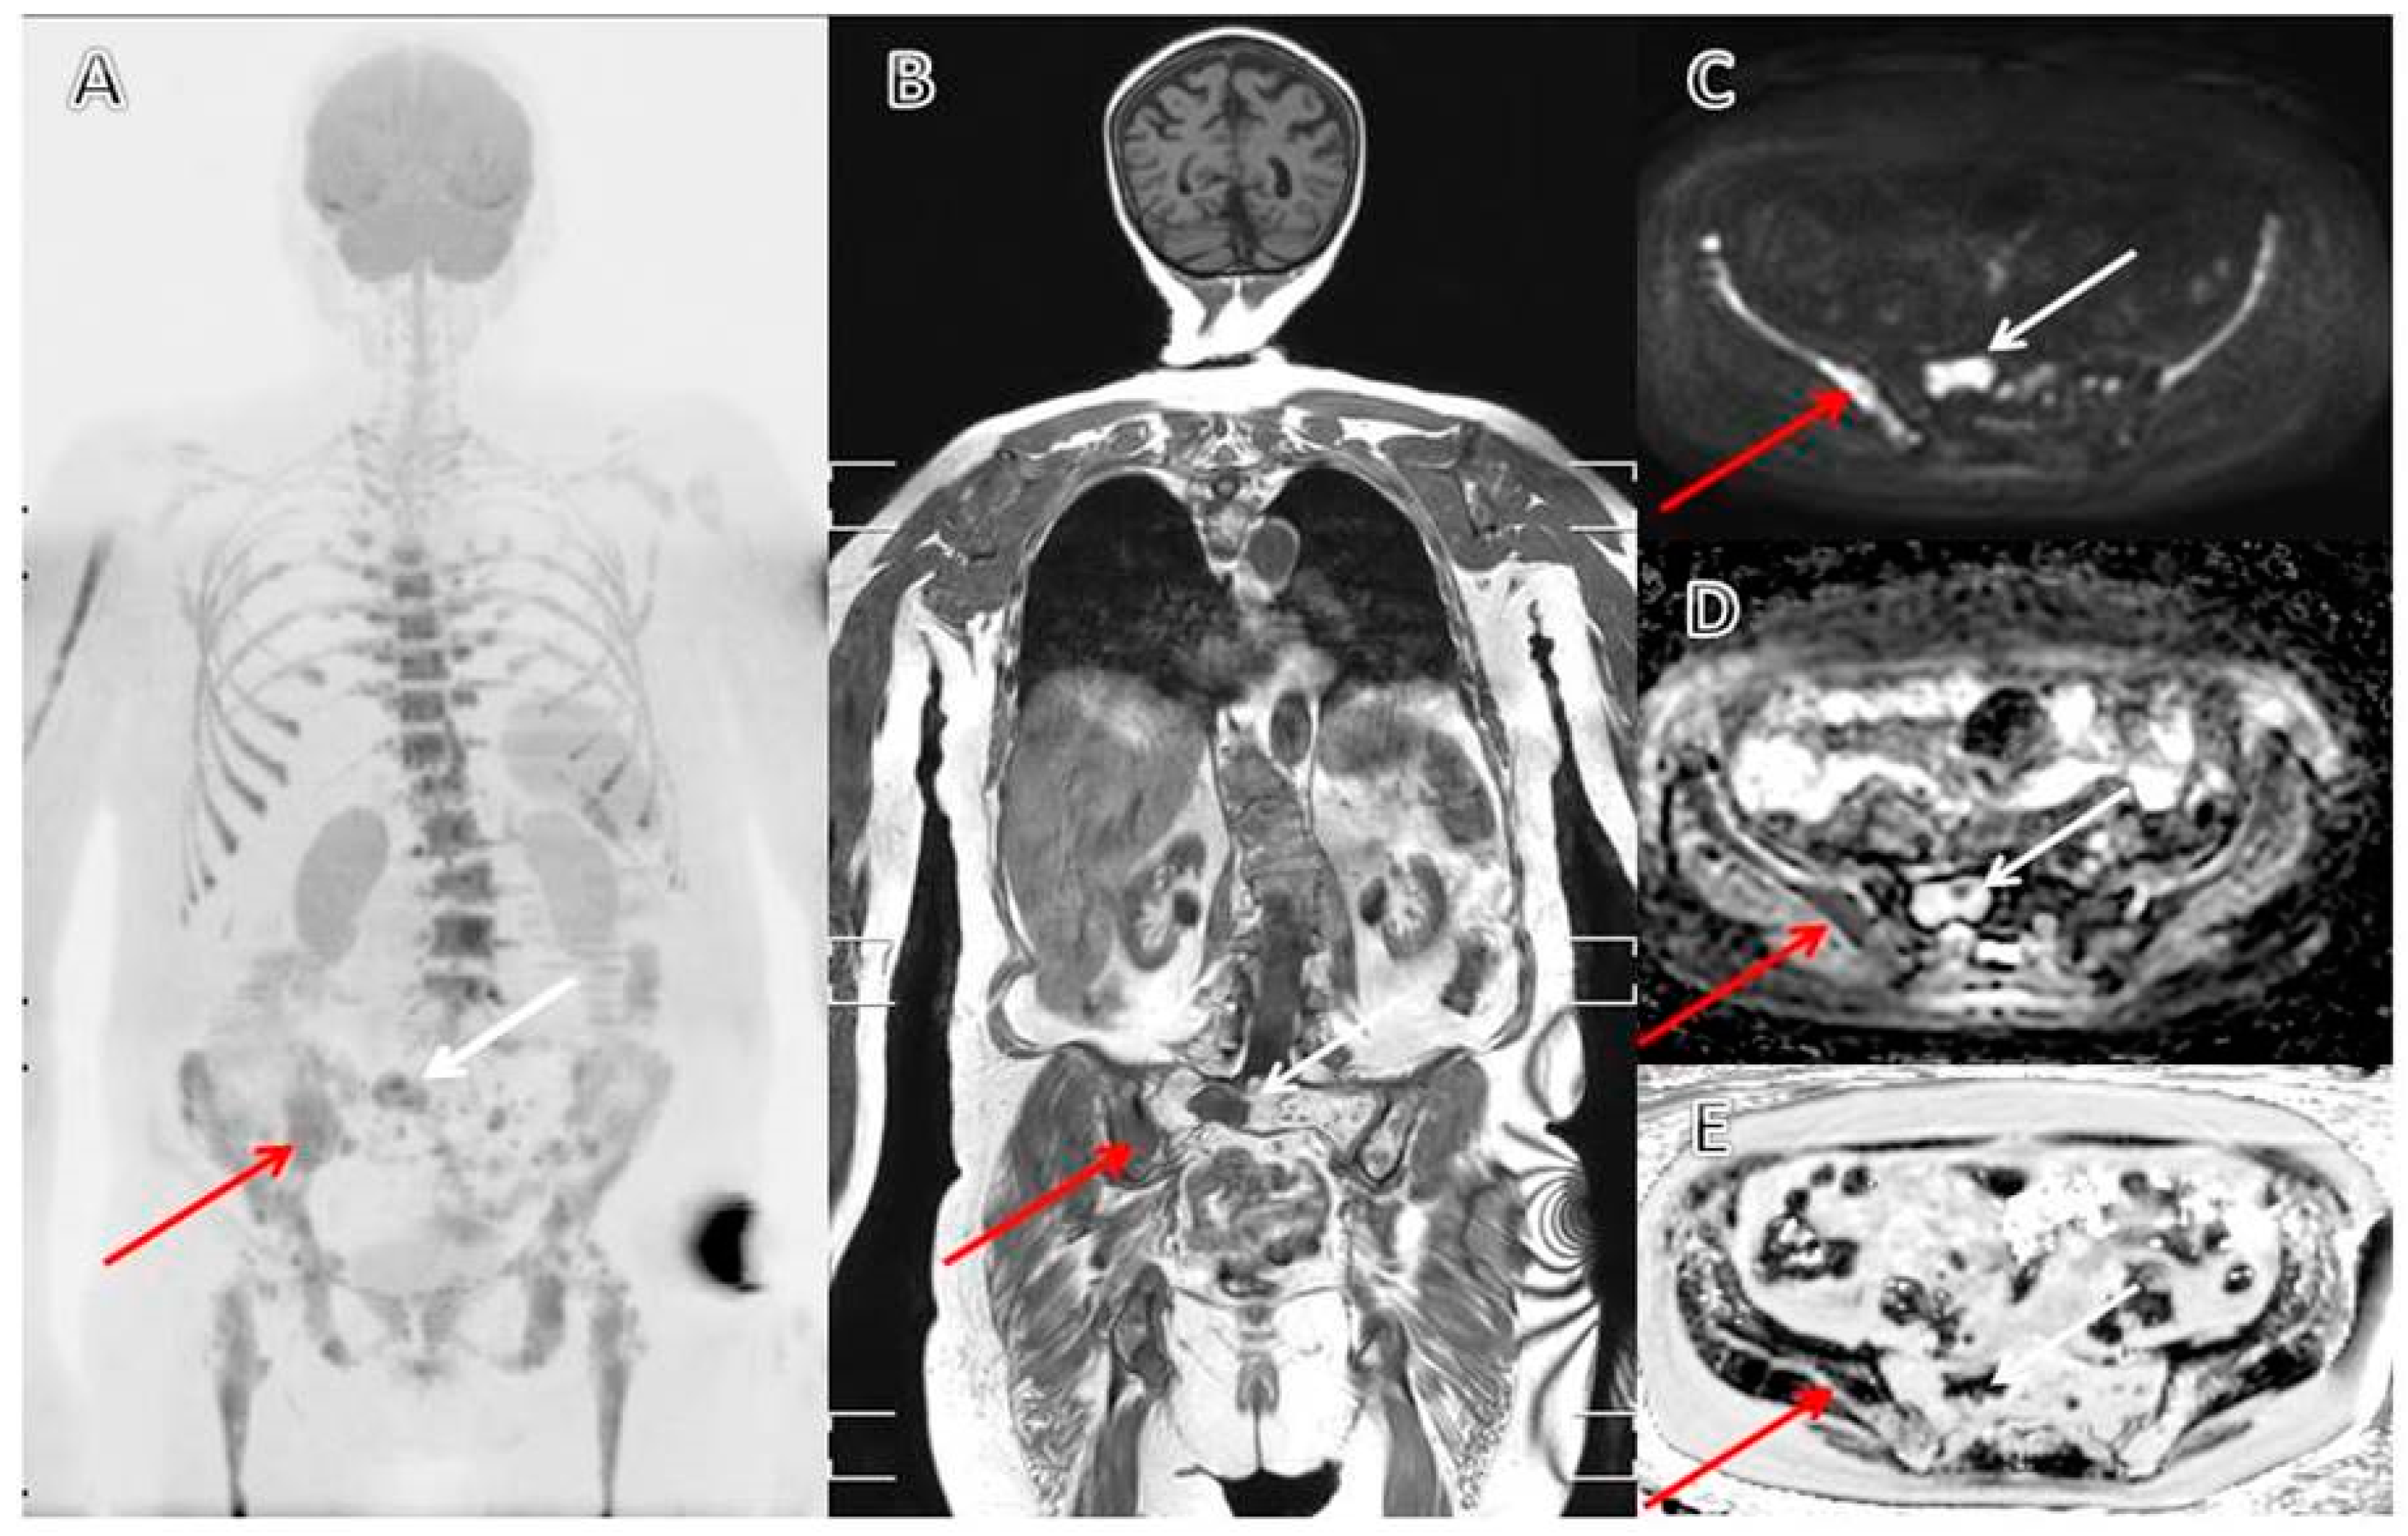

3.4. The Evolving Role of FDG-PET/CT in Multiple Myeloma

- Role of 18 F-FDG PET/CT in the Diagnosis and Management of Multiple Myeloma and Other Plasma Cell Disorders: A Consensus Statement by the International Myeloma Working Group-Clinical Key. Available online: https://www-clinicalkey-com.proxy2-bib.sdu.dk/#!/content/journal/1-s2.0-S1470204517301894 (accessed on 5 March 2020).

- Zamagni, E.; Nanni, C.; Patriarca, F.; Englaro, E.; Castellucci, P.; Geatti, O.; Tosi, P.; Tacchetti, P.; Cangini, D.; Perrone, G.; et al. A prospective comparison of 18F-fluorodeoxyglucose positron emission tomography-computed tomography, magnetic resonance imaging and whole-body planar radiographs in the assessment of bone disease in newly diagnosed multiple myeloma. Haematologica 2007, 92, 50–55. [Google Scholar] [CrossRef] [PubMed]

- Bartel, T.B.; Haessler, J.; Brown, T.L.Y.; Shaughnessy, J.D.; van Rhee, F.; Anaissie, E.; Alpe, T.; Angtuaco, E.; Walker, R.; Epstein, J.; et al. F18-fluorodeoxyglucose positron emission tomography in the context of other imaging techniques and prognostic factors in multiple myeloma. Blood 2009, 114, 2068–2076. [Google Scholar] [CrossRef]

- Zamagni, E.; Patriarca, F.; Nanni, C.; Zannetti, B.; Englaro, E.; Pezzi, A.; Tacchetti, P.; Buttignol, S.; Perrone, G.; Brioli, A.; et al. Prognostic relevance of 18-F FDG PET/CT in newly diagnosed multiple myeloma patients treated with up-front autologous transplantation. Blood 2011, 118, 5989–5995. [Google Scholar] [CrossRef]